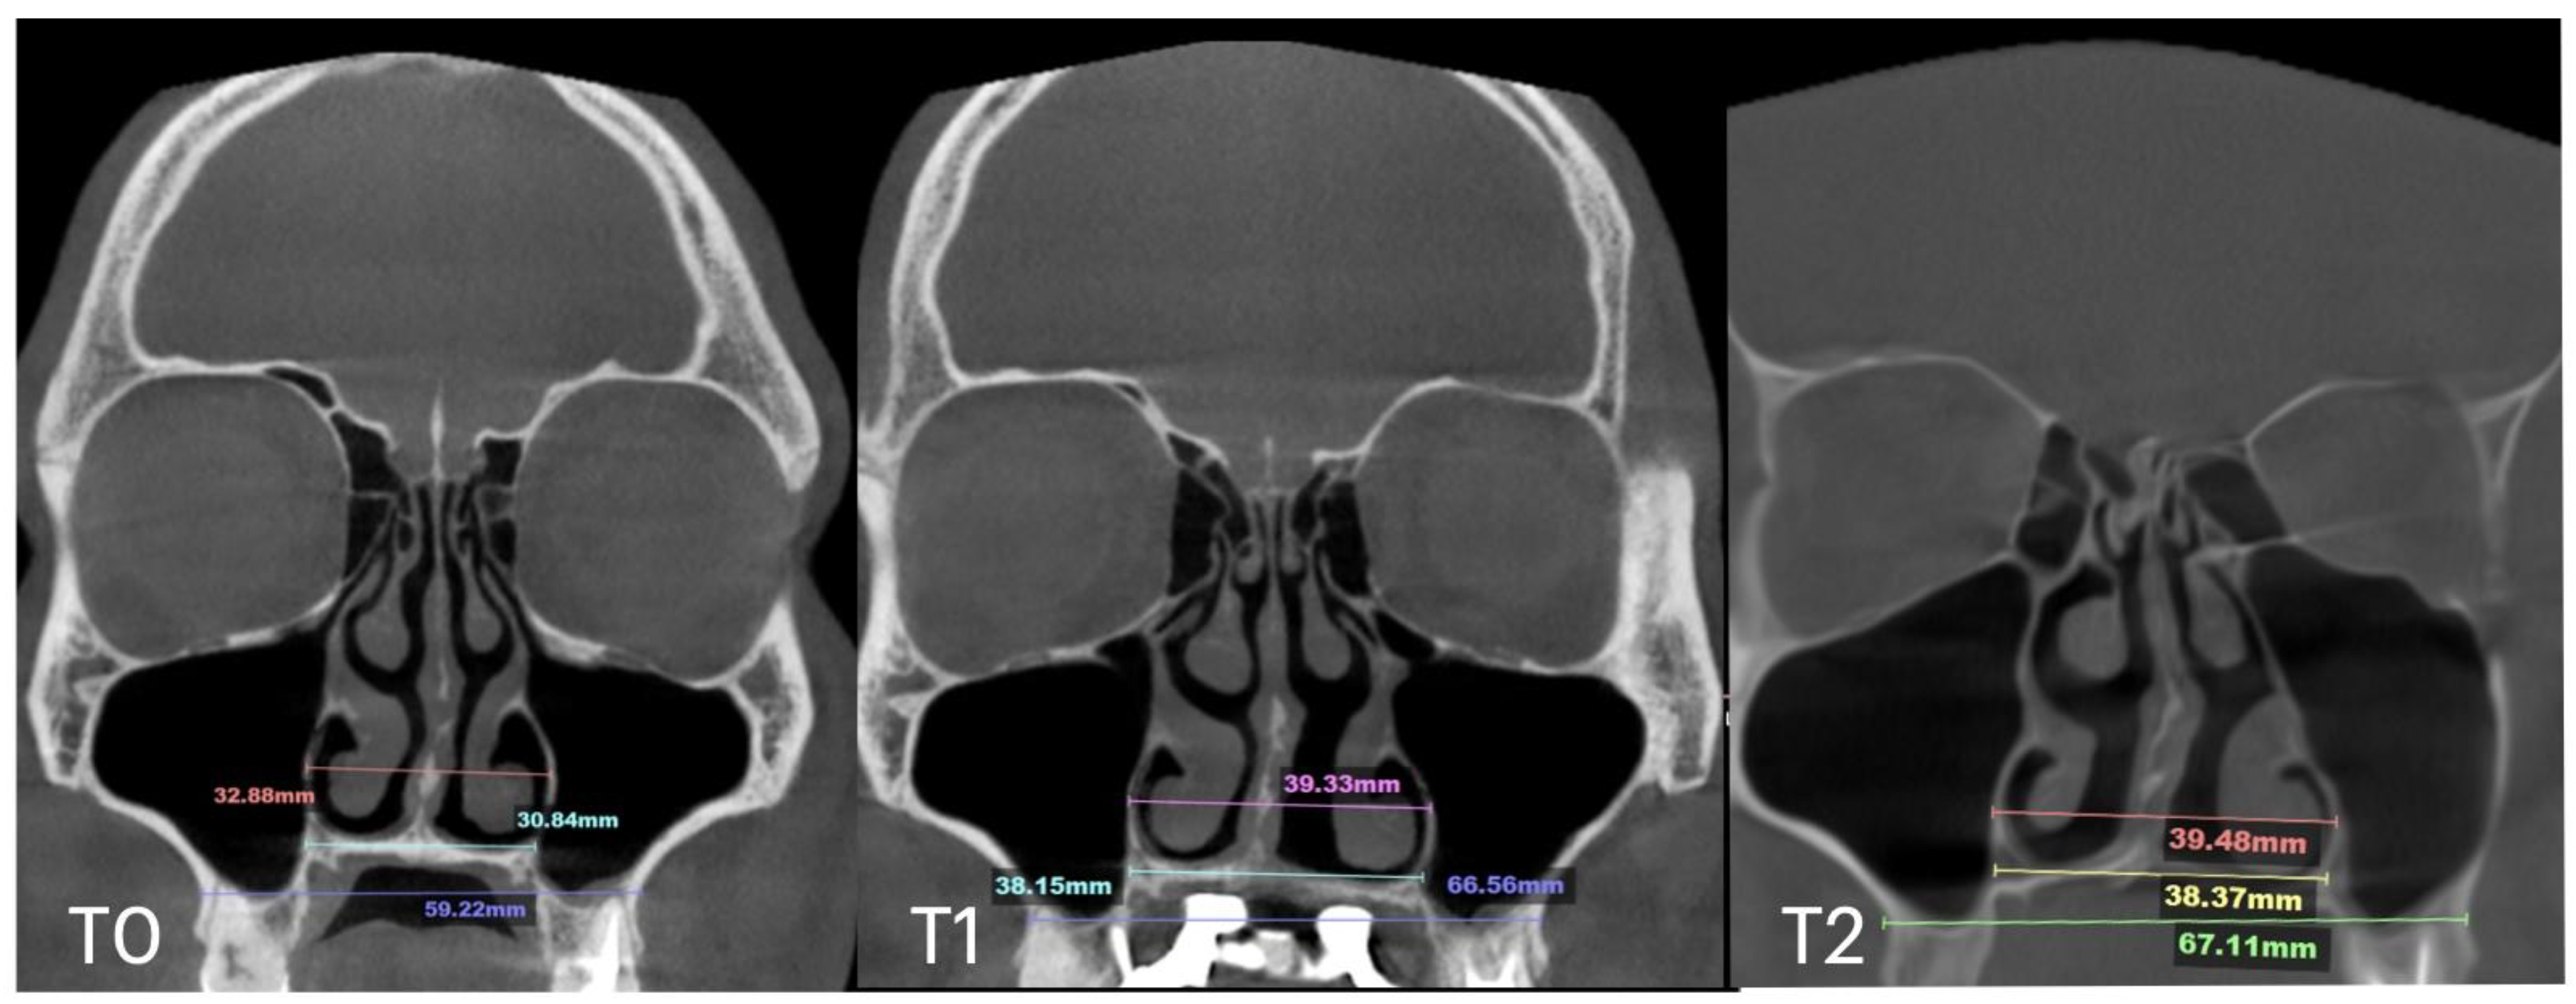

| Nasal Base Width, mm | Maxillary Base Width, mm | Lateral Nasal Width, mm | Inter-Pterygoid Distance, mm | Midpalatal Suture Separation, mm | |||||||||

|---|---|---|---|---|---|---|---|---|---|---|---|---|---|

| T0 | T1 | T2 | T0 | T1 | T2 | T0 | T1 | T2 | T0 | T1 | T2 | T1 | |

| Case A | 30.84 | 38.15 | 38.37 | 59.22 | 66.37 | 67.11 | 32.8 | 39.33 | 39.48 | 28.01 | 32.88 | 33.38 | 10.5 |